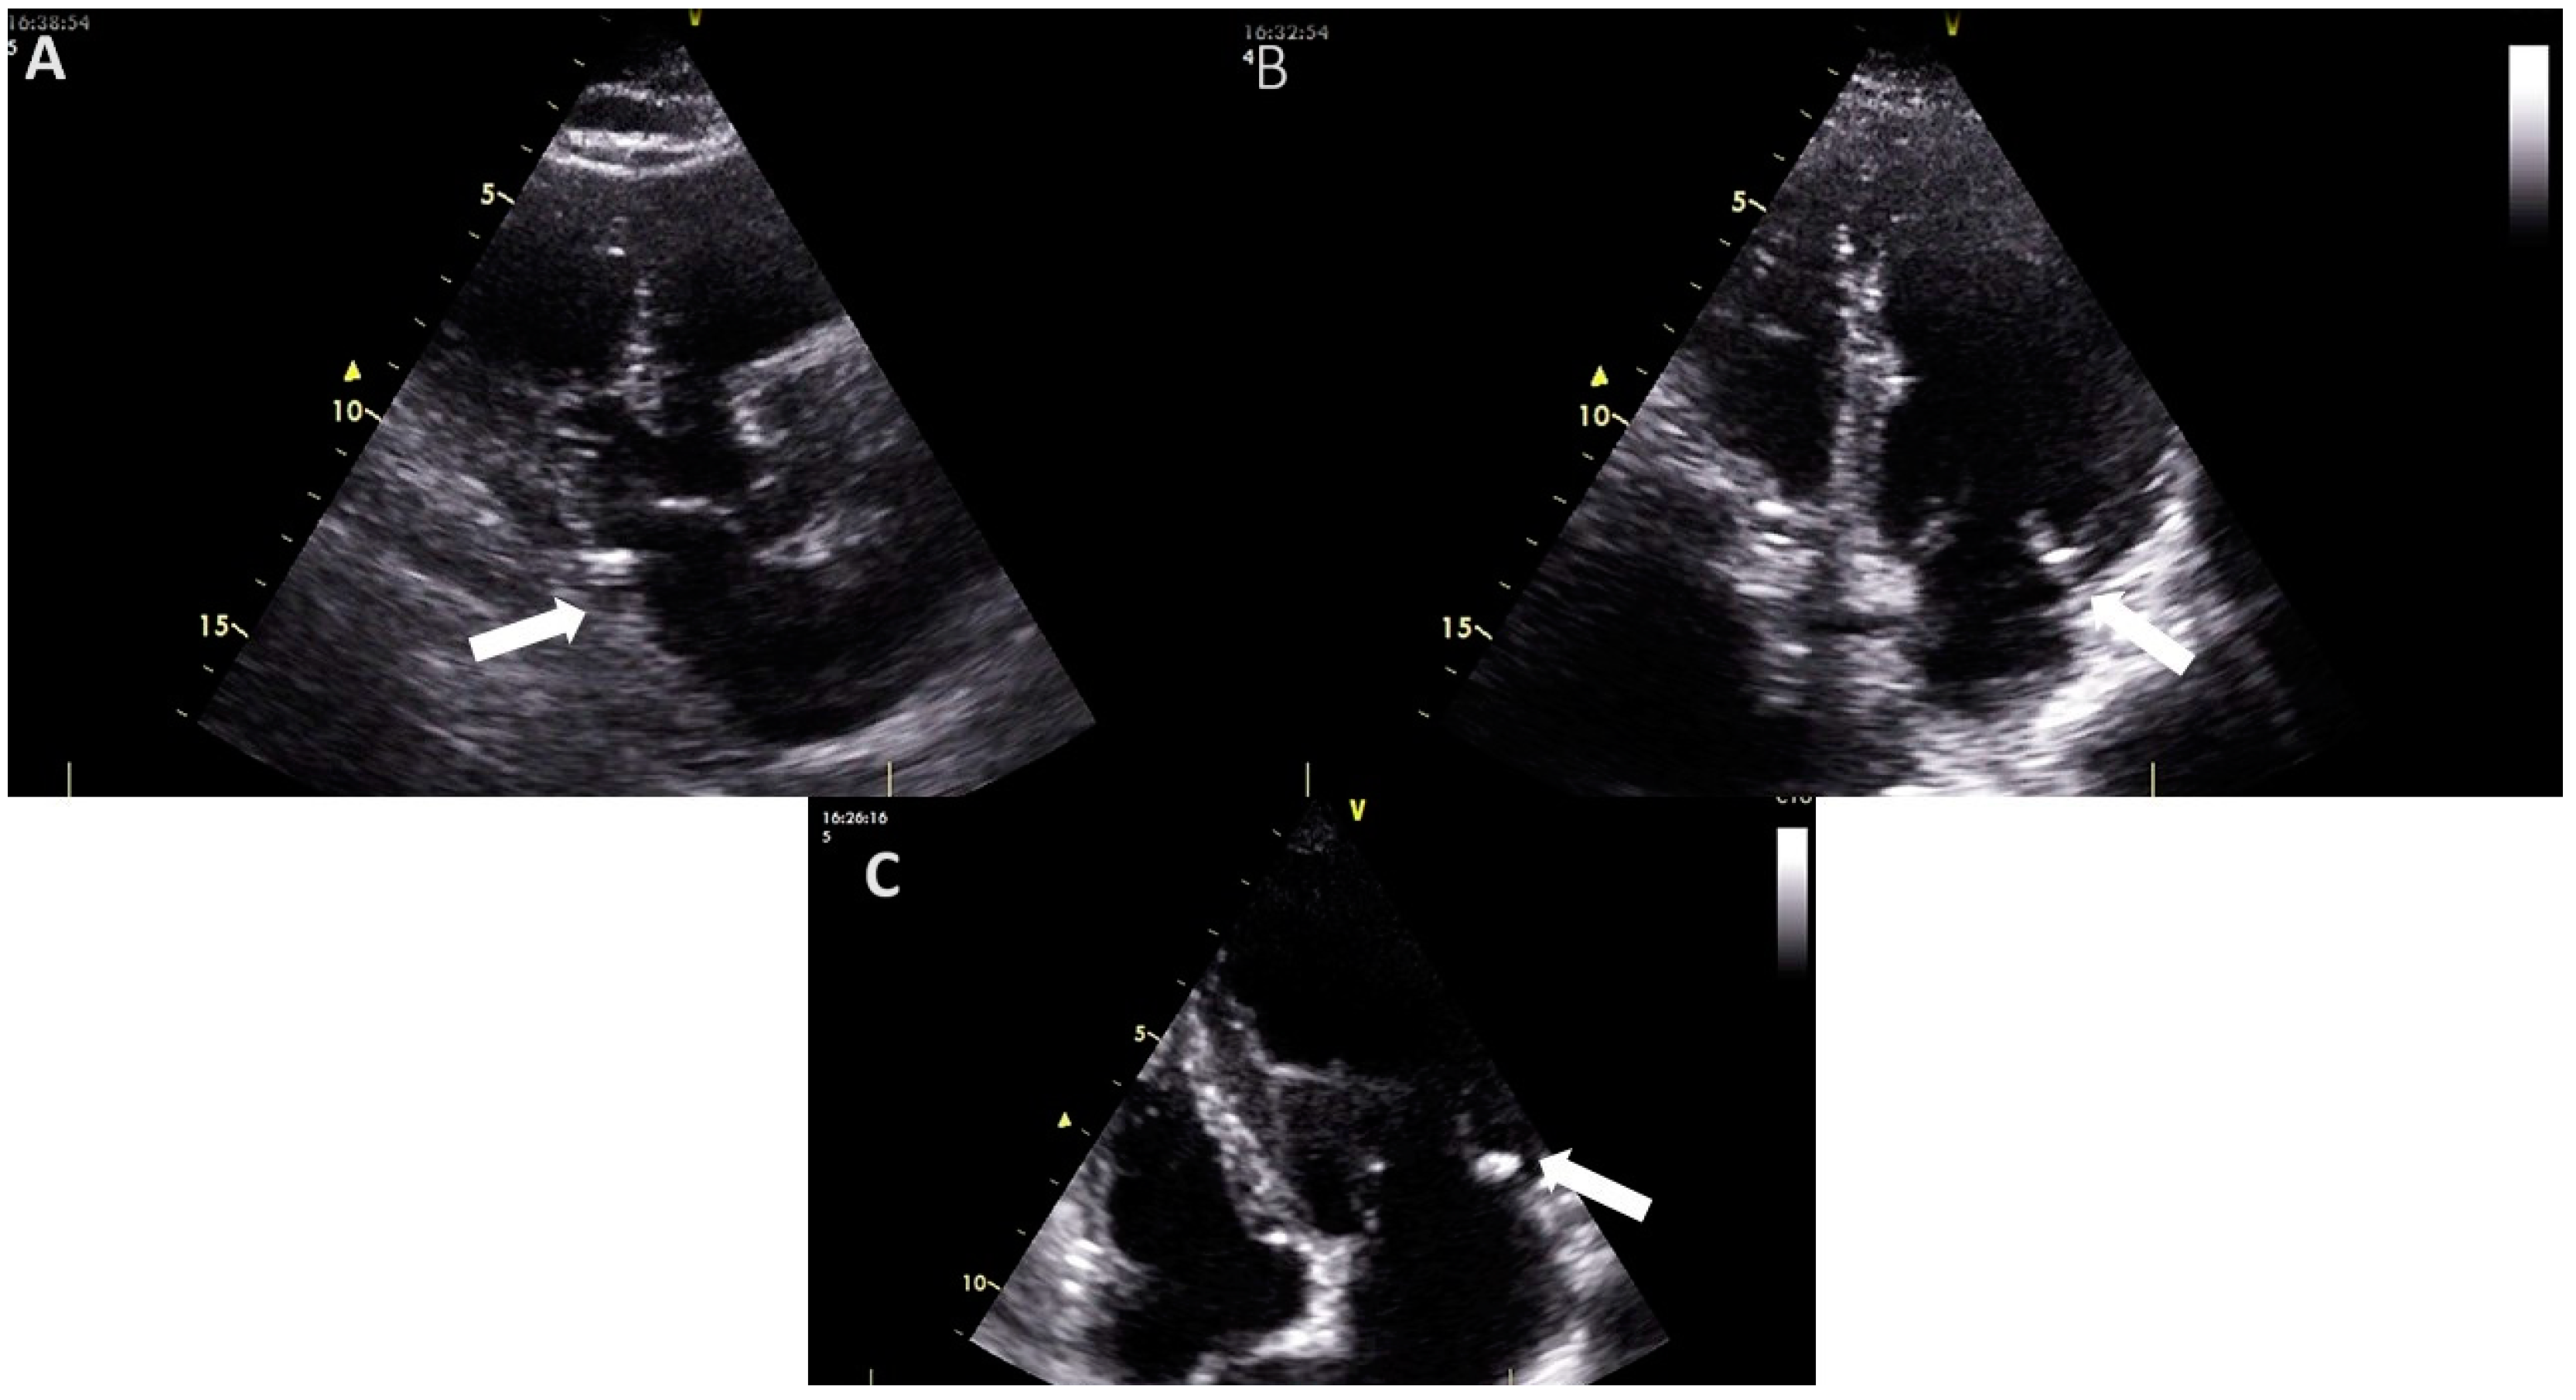

2. Mitral Annular Calcification: From Definition to Diagnosis and Assessment